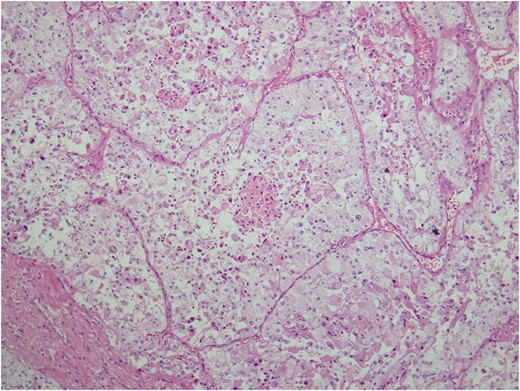

Histologic sections of the mass show distinct variably sized and shaped collections of uniform polygonal tumor cells, separated by fibrovascular septa and delicate capillary-sized vascular channels lined by flattened endothelium at low magnification (Fig. 5). Within the tumor nests, there is loss of cellular cohesion and necrosis of the centrally located cells in the nests results in the pseudo-alveolar pattern (Fig. 6). Vascular invasion is also present (Fig. 7). The individual tumor cells have distinct cell borders and abundant eosinophilic to clear, somewhat granular cytoplasm surrounding a central nucleus with variably sized nucleolus. Nuclear atypia is rarely seen. Mitotic figures are uncommon. The cells contain rhomboid or rod-shaped crystalline inclusions that are faintly apparent on routine histology and are better demonstrated with periodic acid-Schiff stain after diastase digestion (Fig. 8).

Loss of cellular cohesion and necrosis of the centrally located cells in the nests.